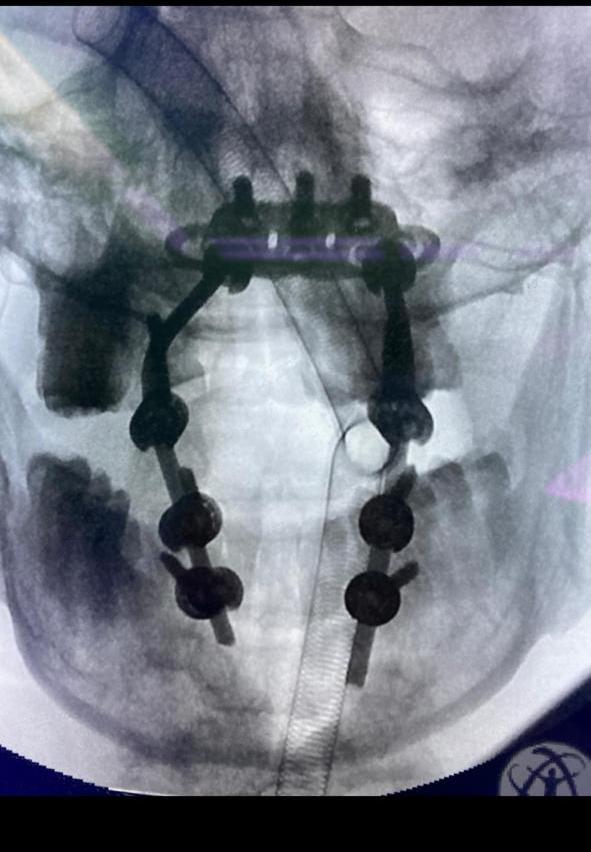

تمكن فريق طبي بمستشفى الملك عبدالله ببيشة بإنقاذ حياة مصاب خمسيني من شلل رباعي مؤكد، إثر تعرضه لحادث مروري.

وأوضحت صحة بيشة أن المصاب قد حضر لقسم الطوارئ بالمستشفى وقد كان يعاني من ضعف شديد في حركة الطرف العلوي الأيمن والسفلي وألم شديد في الرقبة، وبعد إجراء الفحوصات الطبية والأشعة التشخيصية أظهرت تعرضه لكسور وخلع مابين الفقره الأولى والثانية العنقية من العمود الفقري.

وبينت بأن الفريق الطبي المختص قام بإجراء عملية جراحية لإزالة الضغط على الحبل الشوكي وتثبيت الفقرات وإرجاعها لوضعها الطبيعي وتثبيتها بمسامير وقضبان طبيه مابين الجمجمة والفقرة الثالثة العنقية.

الجدير بالذكر ان المصاب قد خرج من المستشفى وهو يتمتع بصحة جيدة ولله الحمد، وأن الفريق المختص مازال يتابع حالته من خلال مراجعته للعيادات الخارجية.